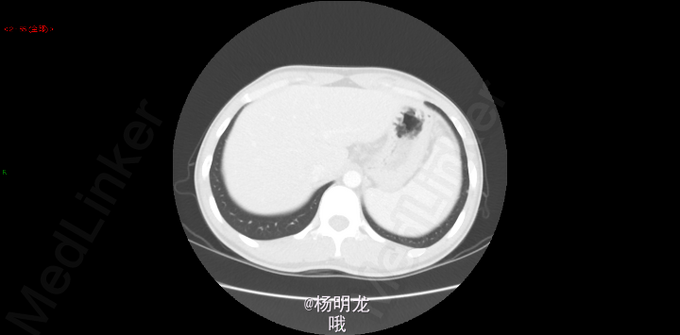

2014.9因大便带血,行肠镜检查,病理提示直肠癌。 2014-10-8胸部CT:双肺新出现多发微小结节,大者约0.2cm,高度警惕肺内转移。 遂于我院行FOLFIRI方案化疗,10周期。

术前诊断 直肠癌 升结肠癌术后 双肺多发结节 转移瘤? 名称:开腹直肠癌切除,结肠造口术(Hartmann术) 探查:右上腹粘连,肝脏只探及部分,质地略韧,未触及肿物。直肠肿物上端位于盆底腹膜返折处,侵及腹膜,与左侧精囊粘连紧密。肿瘤4x4x3cm。无腹水,右腹部原术区未触及异常。 由于盆腔狭窄、粘连,向深部游离骶前间隙时出现静脉出血,紧急压迫止血。通过压迫不再出血后,于肿瘤上缘15 cm切断乙状结肠,于肿瘤下缘3cm以闭合器闭合直肠并切断直肠,切除肿瘤和肠管。 发生骶前静脉大出血,估计有2000ml。输血红细胞4u,血浆4u。